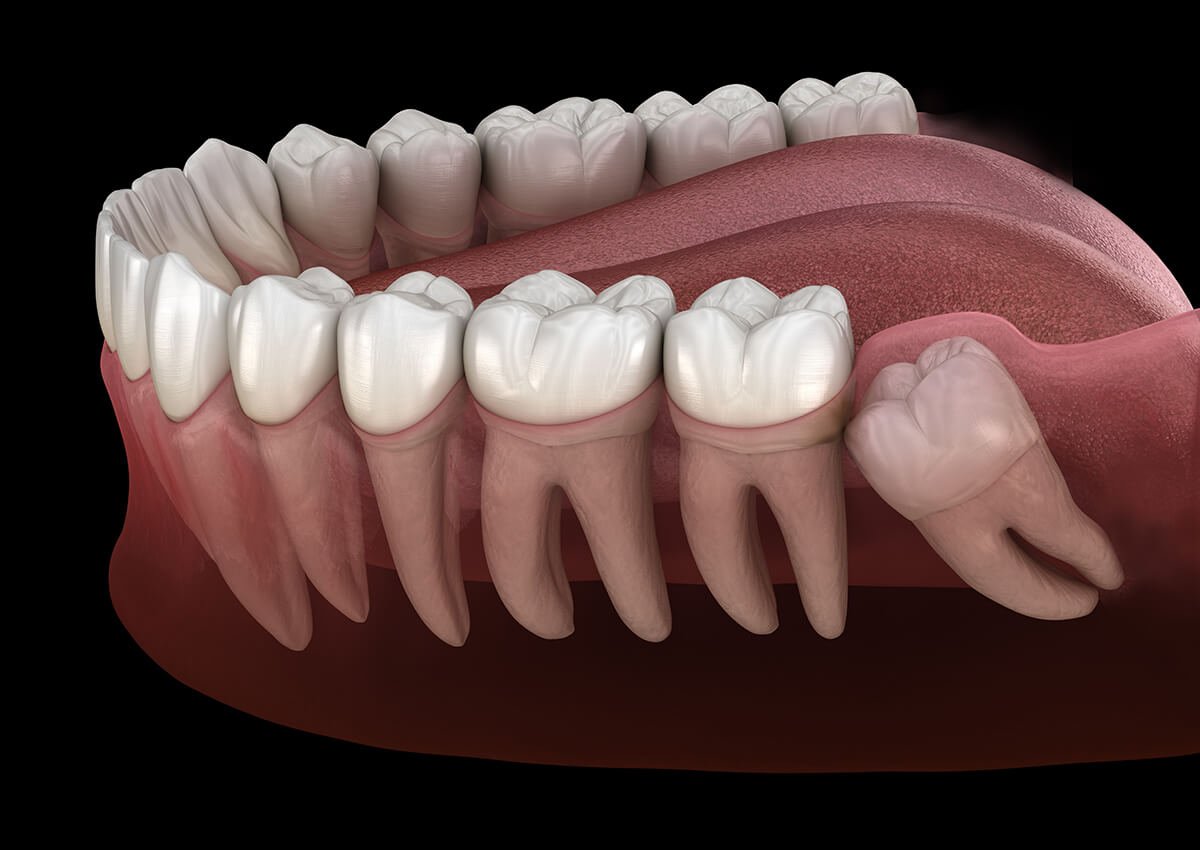

Wisdom teeth are the last molars in your mouth. Most people have four wisdom teeth. However, some may have fewer. These teeth usually appear in late teenage years.

Sometimes, there is no space for them. As a result, they grow in the wrong direction. This condition is called impaction. Impacted teeth often cause pain and infection. Therefore, wisdom tooth removal becomes necessary.